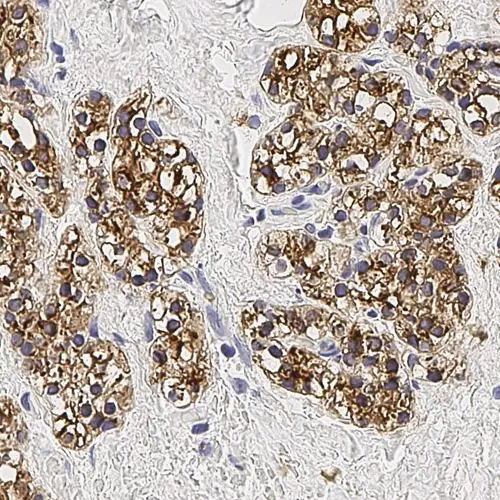

Human parathyroid adenoma: immunohistochemical staining for Parathyroid Hormone. Note membrane/cytoplasmic staining of tumor cells. Parathyroid Hormone: clone 105G7